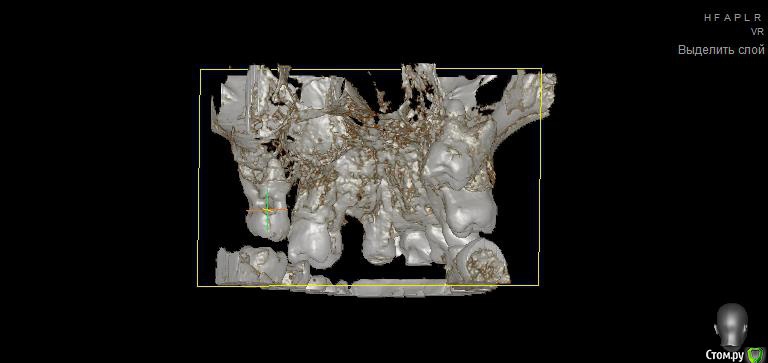

Просьба ко всем не равнодушным! Глянуть КТ верхней челюсти, 27 зуб  и место где удалили 16, может ещё где-то могут быть проблемы.  На фото видно где покраснение на дёснах, в этих местах возникают боли при движении головой. Бывает боль слева если засыпаю на левой стороне. Набуханий или флюсов нигде не видно.Прошу делиться мнениями, для меня это очень - очень важно. Стоматолог визуальных проблем на месте удалённого зуба не видит, всё зажило.

По данным КТ в зоне удалённого зуба 16 ничего особенного, разве что, ретенированный (непрорезавшийся) зуб 18.

Зуб 27 требует внимания, необходим очный осмотр.

Также стоит обратить внимание на зубы 21 и 24